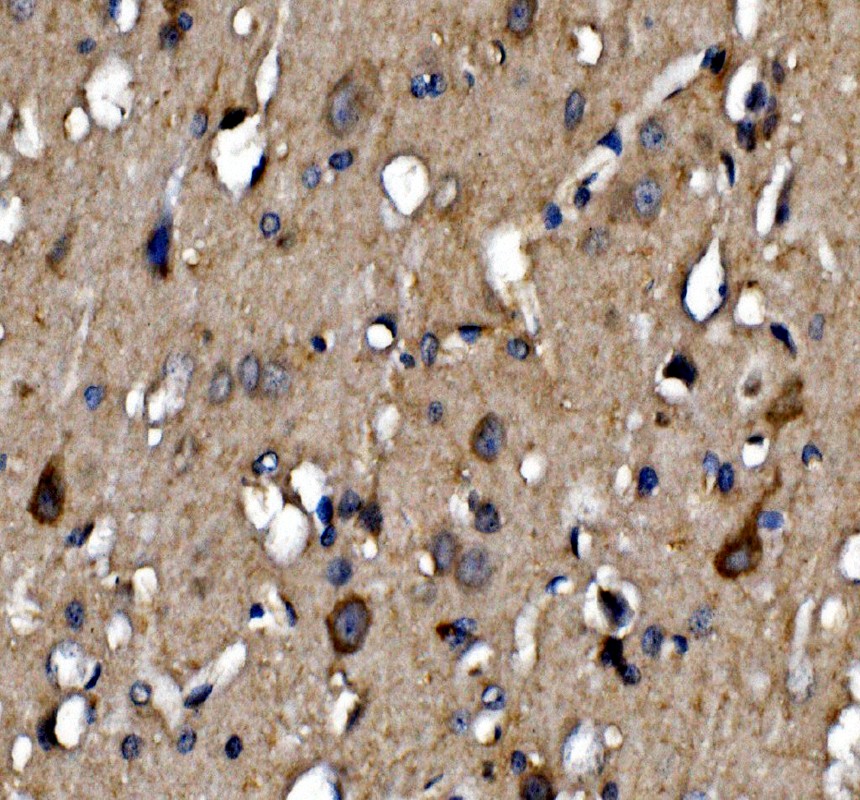

IHC analysis of NMDAR2A/GRIN2A using anti-NMDAR2A/GRIN2A antibody (PA1058-1).

NMDAR2A/GRIN2A was detected in a paraffin-embedded section of human brain tissue. The tissue section was incubated with rabbit anti-NMDAR2A/GRIN2A Antibody (PA1058-1) at a dilution of 1:200 and developed using HRP Conjugated Rabbit IgG Super Vision Assay Kit (Catalog # SV0002) with DAB (Catalog # AR1027) as the chromogen.